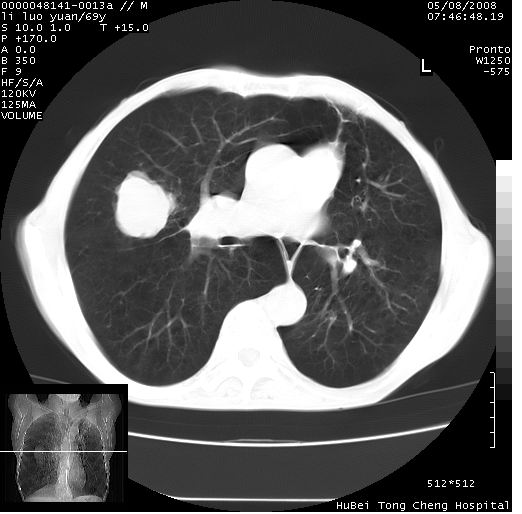

临床资料:老年患者,咯血、消瘦

影像表现:桶状胸,双肺纹理纤细、紊乱,透过度增高,肺野内可见多发、散在、大小不等的无壁高透过影,右肺中叶外侧段分叶样软组织占位,左上肺纤维索条样密度影,相应层面左侧胸腔轻度萎陷,纵隔左移。

影像诊断:1、慢支、肺气肿、双下肺野肺大泡形成

2、左上肺陈旧性肺结核

3、右肺中叶外侧段占位 考虑肺ca可能性较大、建议增强及痰检脱落细胞